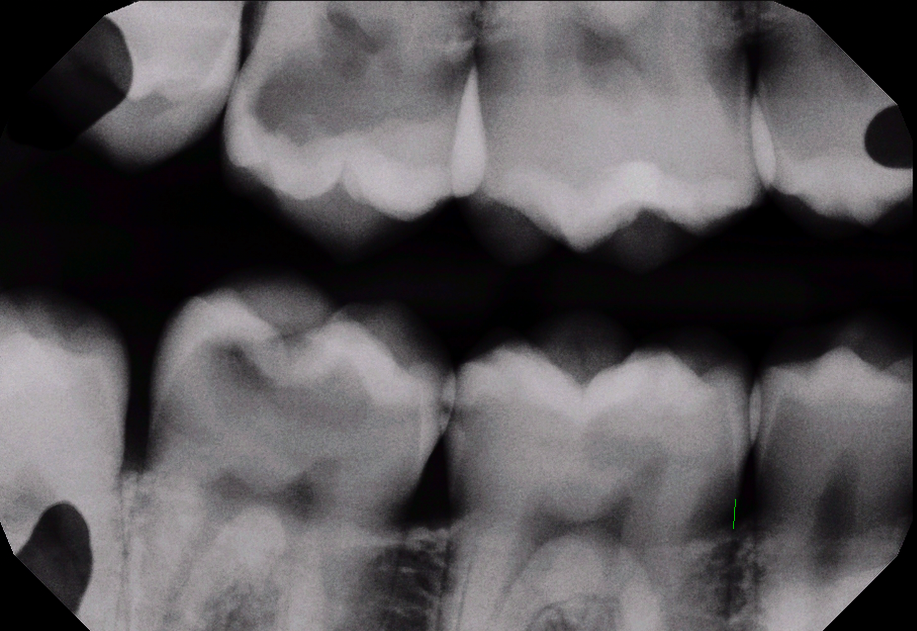

Improve patient education with AI-driven caries detection. Dentists who use Sugarbot benefit from consistent, real-time x-ray analysis.

Original bitewing With AI overlay

Before